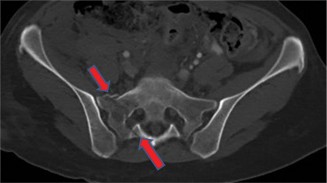

A 67-year-old female presents to your clinic with pelvic and groin pain for 5 days after a low-impact fall fr…